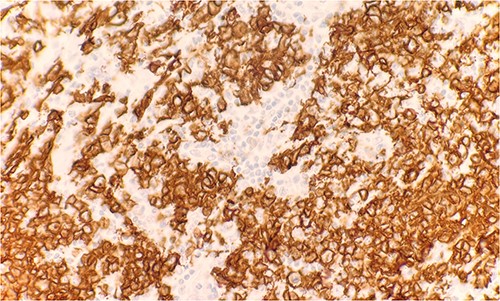

Microscopic examination reveals skin and subcutaneous tissue with atypical nodular nested lymphoid infiltrate in the dermis. The infiltrate is composed of intermediated cells with irregular nuclei, dispersed chromatin and variably conspicuous nucleoli mixed with large cells (Fig. 1). The atypical cells are positive for CD20 (Fig. 2) and BCL6 (Fig. 3). The morphological findings along with the skin location are consistent with primary cutaneous follicle center lymphoma (PCFCL).

Immunohistochemical stain reveals atypical lymphoid cells are positive for BCL6. IHC 40×.